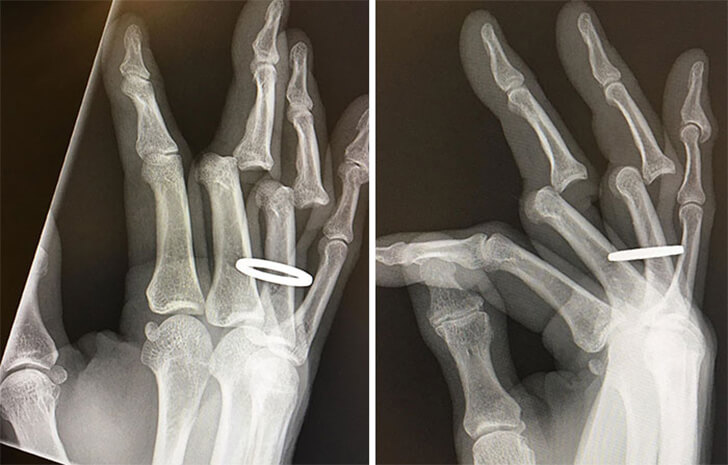

A Handy Ring Rescue

We’ve got an X-ray that tells the story of a tight squeeze. A person had to cut off their ring before doctors could realign their bones to their proper position. The hands are shown, post-ring removal, ready for the fix-up.

It’s a common issue where rings can cause complications, especially in medical procedures or emergencies. This X-ray is more than just bones and joints; it’s a snapshot of a ring’s journey from a symbol of commitment to a tiny but significant medical hurdle.